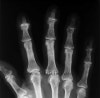

X-ray에서 낭종 근처의 골극(osteophyte)를 거의 발견할 수 있습니다.

X-ray : Digital mucous cyst